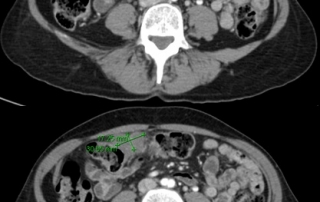

La biopsie guidée sous scanner de la masse mésentérique conduit au diagnostic de lymphome diffus à grandes cellules B CD20+ avec des zones évoquant la transformation d’un lymphome folliculaire en lymphome agressif.

Biologie : hémogramme normal, LDH augmentées à 720 UI. Biopsie médullaire et le myélogramme et l’immunophénotype médullaire montre une infiltration médullaire par un lymphome folliculaire à petites cellules, l’examen cytogénétique retrouve une translocation t(14 ;18), et l’étude en biologie moléculaire un réarrangement du gène Bcl2.

Classement LNH diffus à grandes cellules CD20+ transformation d’un lymphome folliculaire, stade IV péritonéal et médullaire, OMS = 1, LDH augmentées. L’infiltration médullaire à petites cellules caractérise la transformation du lymphome folliculaire, et n’a pas la valeur pronostique péjorative d’une infiltration médullaire d’un lymphome à grandes cellules.

Décision Traitement initial par R-ACVBP x 4 cycles avec prophylaxie neuro-méningée. Recueil d’un greffon CSP après 4ème cycles. Consolidation par métothréxate à hautes doses et conditionnement BEAM autogreffe de cellules souches sous réserve d’obtention d’une réponse complète

Imagerie évaluation de la réponse :

Le traitement R-ACVBP a été choisi plutôt que R-CHOP en raison de la transformation du lymphome folliculaire et de la masse tumorale volumineuse.